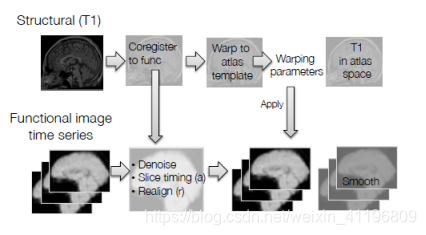

图1为fMRI数据预处理流程

在这个模块中我们会讨论将图像与脑图谱模板(atlas template)配准及平滑(smoothing)的过程。通常来说,每个人的大脑都是不同的,两个个体的大脑尺寸差异可以达到30%,大脑形状也可能存在显著差别,所以标准化(normalization)所做的正是通过拉伸、压缩以及卷绕使得扫描得到的大脑与标准大脑模板一致。这对于组分析(group analysis)而言很重要,因为我们想要对比不同的大脑,当我们关注某一个体素(voxel)时,我们希望能够在所有被试个体的扫描图像中看到这个体素,这就需要所有的大脑“匹配”至同一个标准脑空间(standard brain space)。所以高分辨率的T1结构像现在又被配准至标准空间(normalized space),如下图2所示。

注:从图 1的流程图中可以看出,课程中所讲的标准化是先将高分辨率的T1结构像与标准模板(此处的标准模板是高分辨率的结构像标准模板)进行配准,再直接将这些配准参数应用于功能像上(因为功能像之前已经与结构像进行过一次配准),这也是目前比较普遍的一种做法,因为T1结构像分辨率高,大脑内部结构可精准对齐。但还有另外一种做法,可以直接将功能像与标准模板(此处的标准模板是低分辨率的功能像标准模板)进行配准,这种做法在SPM软件中比较常见,不需要借助T1结构像,但在对齐效果上较差。

最后,再来回顾一下fMRI数据预处理的流程(如下图 5所示),扫描得到的结构像和功能像都需要进行预处理。结构像,通常是T1加权,需要与功能像进行配准,并配准至标准空间。功能像,通常是T2*加权,需要进行去噪,扫描层时间校正,以及头动校正之后,将标准化过程中结构像的配准参数应用于功能像上,使功能像也配准至标准空间(如MNI脑图谱)。最后,功能像进行平滑,就可以开始数据分析了。

图 5 fMRI数据预处理流